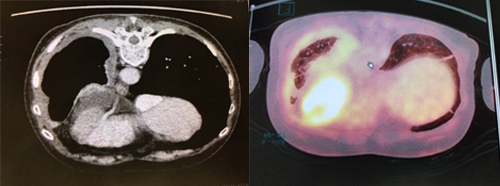

選ぶなら 気道・肺の腫瘍 (呼吸器病New Approach 9) | 飛田 渉 |本 | 通販 医学一般